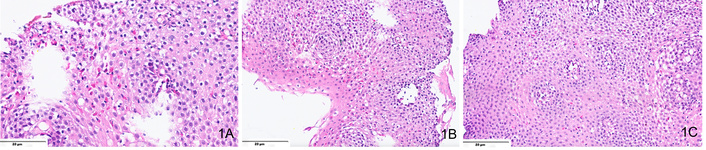

EoE is confirmed by identifying ≥ 15 eosinophils per HPF in esophageal mucosal biopsies (Figure 1). Due to patchy distribution, at least five samples from different regions are recommended for accurate diagnosis [21]. Eosinophil infiltration is typically denser in distal esophageal regions with the presence of white plaques or furrows [12, 20]. Additional histological features include eosinophil degranulation, eosinophilic microabscess, basal cell hyperplasia, spongiosis, dilated intercellular spaces, and papillary elongation [30, 31]. Eosinophil counts vary widely due to differences in biopsy sampling, staining methods, and HPF definitions. Inter-observer variability among pathologists further complicates borderline cases. Endoscopic practices also differ, with inconsistent biopsy numbers and sites affecting diagnostic yield. Standardized protocols and training are essential to improve diagnostic reproducibility across centers.

A microphotograph shows multiple features of eosinophilic esophagitis. Including (A) intraepithelial eosinophilia > 15 eosinophils in one high-powered field (H&E, ×400); (B) basal cell hyperplasia, with basal layer comprising > 15% of the thickness of the squamous epithelium (H&E, ×200), and (C) intercellular edema or “spongiosis” (H&E, ×200).